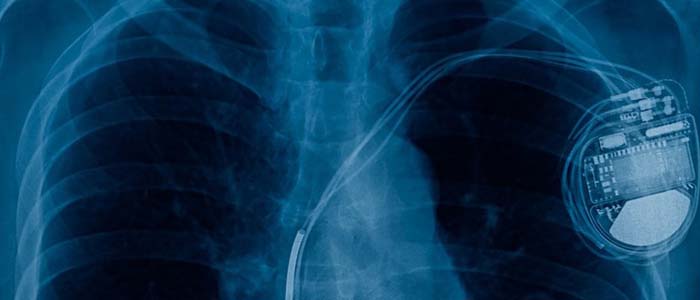

Surgical procedure to implant a device that regulates heart rhythm, ensuring stable and healthy cardiac function.